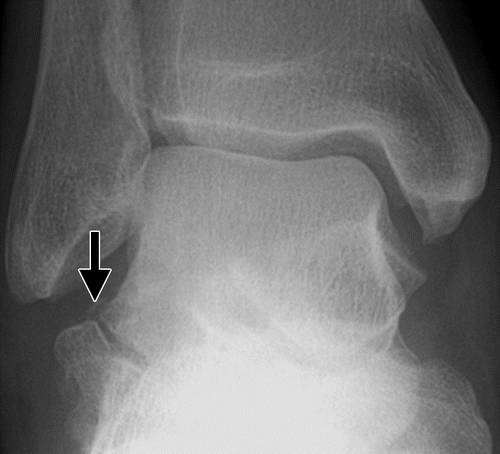

后突骨折通常比内侧结节(Cedell骨折)(30)涉及外侧结节(Shepherd骨折)。 后部过程骨折由于跖骨屈曲引起,导致胫骨和跟骨之间的后部过程的压缩。 这也可能发生在对后踝的直接创伤。

骨折的最可靠的指标是足跟后曲的疼痛,和踝关节在足底屈曲时的骨摩擦音,轻度存在于跟腱之前和距骨后。 由于在与受伤的后外侧结节(31)相邻的凹槽中的屈肌半腱的运动,也可以看到由于拇趾的操作而引起的疼痛。

这种损伤必须与三角骨 - 一个附件后骨小梁区分开来。 在放射照相术中,后过程的断裂显示不规则的边缘(图13),而三角骨是圆形或椭圆形,具有光滑的皮质边缘(图14)。 双侧X线照片的价值有限,因为据报道三分之二的病例是双侧的(32)。 如果射线照片不确定,应进行CT。

X光片显示骨折片段在后及内侧距骨,是诊断后Cedell内侧结节骨折的一个依据。 所提出的机制是在后胫骨韧带与踝关节的背侧附着的背屈和旋前的撕脱(30)。

后突骨折通常与固定和无负重的治疗。 如果保守措施失败,可能需要切除片段(3,31)。